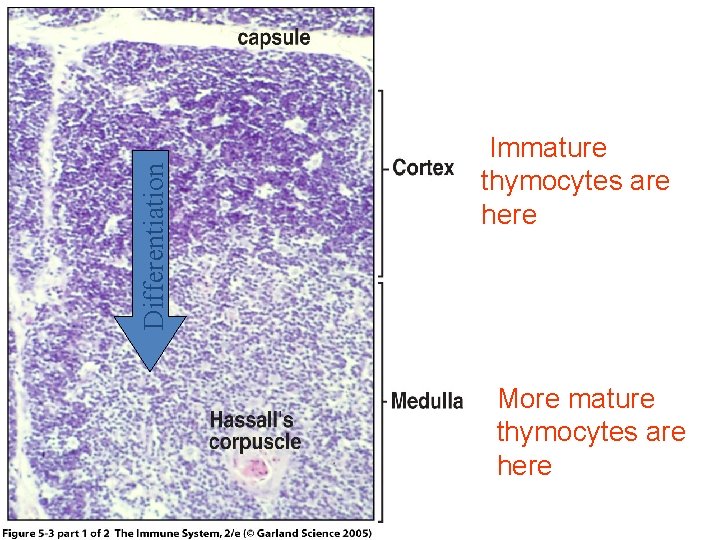

Thymus is the only discrete central lymphoid organ in humans. It produces only T lymphocyte precursors and has no lymphoid nodules. Its reticular cells derive from endoderm and produce no reticular fibers. It is the only organ containing Hassall’s corpuscles. Its age-dependent structural atrophy or involution is also unique among lymphoid organs. 2 lobes are joined and covered by a thin loose connective tissue capsule that penetrates the lobes as septa, dividing each lobe into incomplete lobules. Cortex. This is the dark-staining periphery of each lobule. Small lymphocytes predominate

Medulla. In effect, each thymic lobe has a single medulla that extends into the core of each of the lobules. The light staining of the medulla reflects the presence of more epithelial reticular cells and fewer lymphocytes than in the cortex. The spheric Hassall’s corpuscles (30 -150 m in diameter) are composed of concentric layers of flattened epithelial reticular cells. With age, cells in the core of the corpuscles may die and calcify. Functions: 1. T lymphocyte production. 2. Blood -thymus barrier. 3. Production hormone - thymosin

Differentiation Figure 5 -3 part 1 of 2 Immature thymocytes are here More mature thymocytes are here